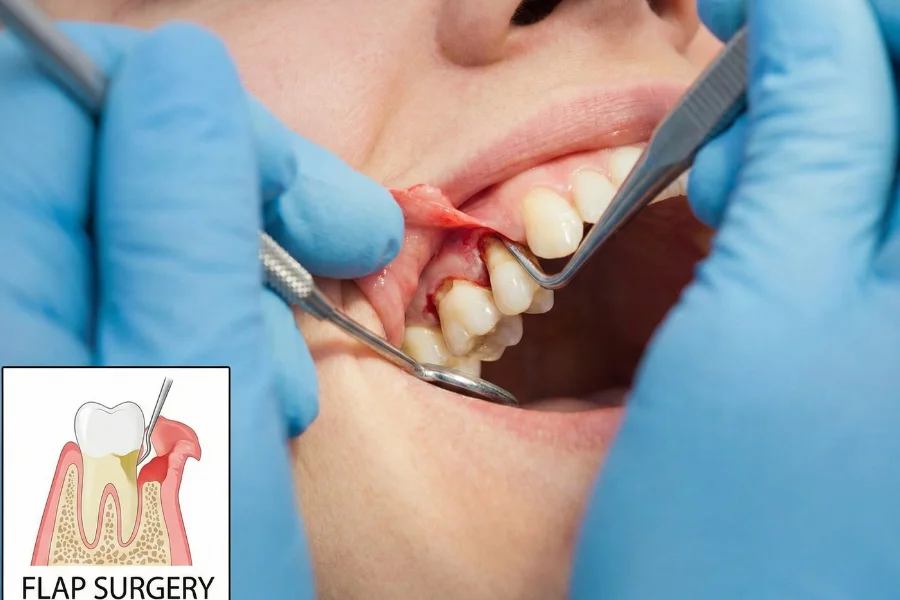

Flap surgery is a gum treatment where the gums are gently lifted to access deep infection beneath the gum line. The infected tissue, plaque, and tartar are removed, and the gums are repositioned securely to allow proper healing. This procedure helps control advanced gum disease and prevent tooth loss.

The treatment process usually includes:

Detailed gum examination and imaging

Local anesthesia for comfort

Deep cleaning of roots and infected areas

Repositioning and securing gums

Follow-up visits for healing assessment